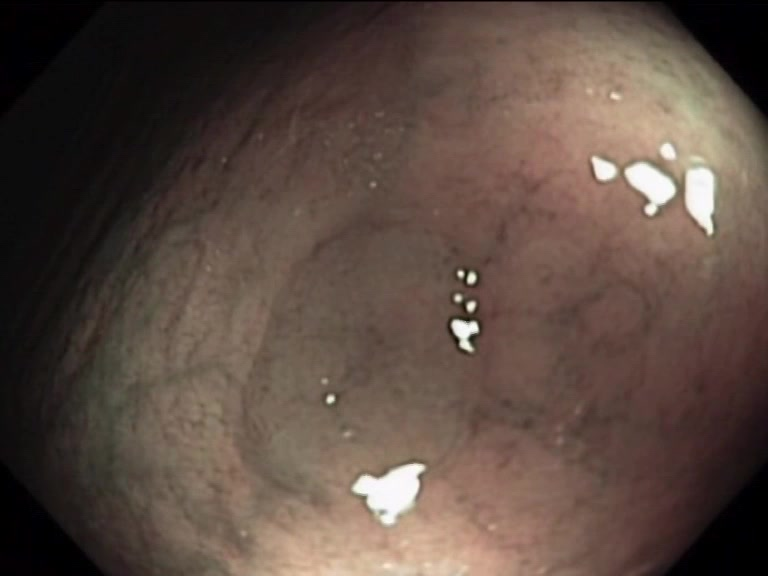

| Lesion | White Light Frame | NBI Frame | White Light Video | NBI Video | Camera Calibration |

| serrated_01 |  |

|

WL.mp4 | NBI.mp4 | cam.xml |